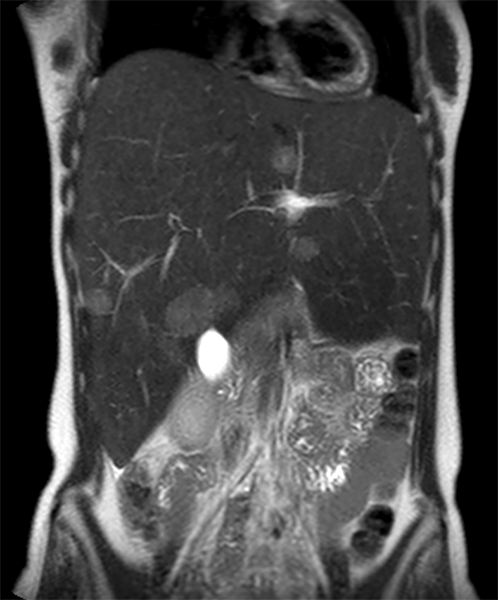

Coronal T2w TSE